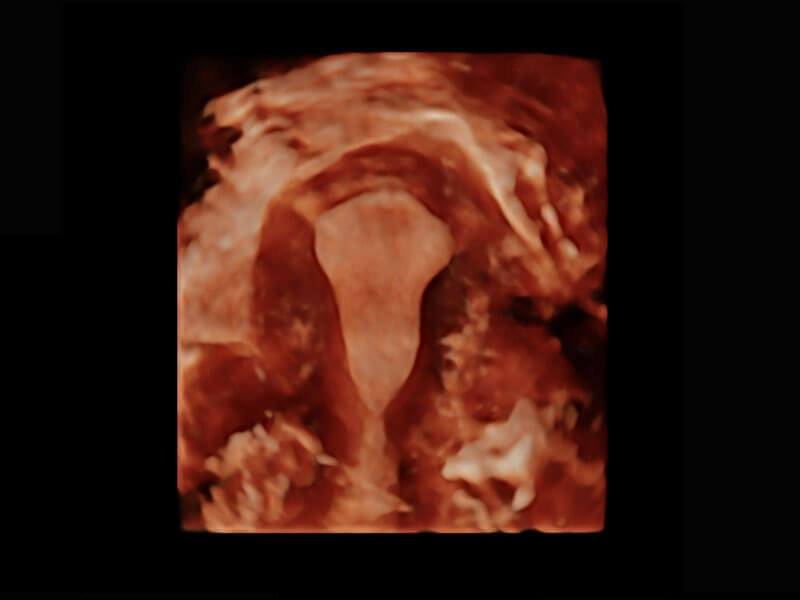

P60搭载一系列胎儿心脏成像技术,实现精细的胎儿心脏评估。

• 胎心容积成像